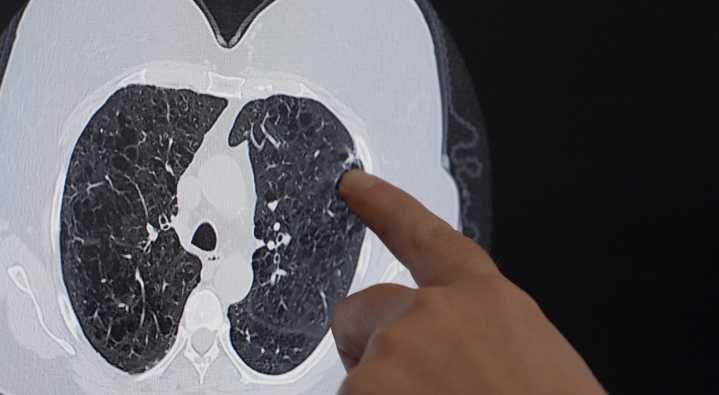

A look at lung cancer screenings in Oklahoma show how much those screenings matter. Oklahoma has among the lowest lung-cancer screening rate in the nation. Doctors say that often means cancer isnt found until its harder to treat.

A spot in the upper right corner of Gwyn Lessens right lung was cause for concern.

It was only her third lung cancer screening ever. The first in September 2022 was fine. Her second in October 2023 was good. November 2024s screening revealed a small nodule.

Lessen, a former smoker, was filled with fear but also gratefulness that the tiny lump was caught early. She had surgery at St. Francis this summer.

Dr. Hope Cordova removed the cancer